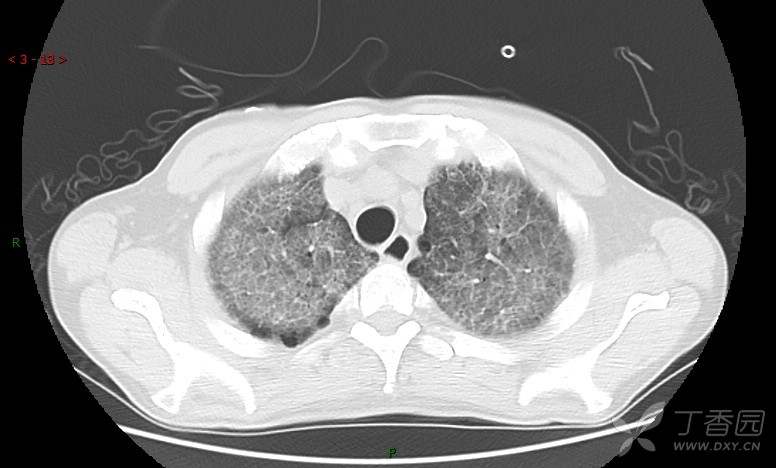

地图+铺路石征=PAP?那升高的CEA怎么说(病例3连发,附其他2例链接)

患者男,42岁,咳嗽半年余,加重伴憋喘2月余。

肺内弥漫性网状结节影,PET-CT却无阳性病灶,这是?(附其他2例链接)